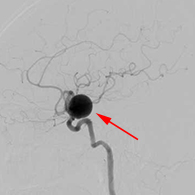

<実際の手術所見>

<手術中の脳血管撮影画像>

瘤(こぶ)は消失

患者様は術前からあった左視力低下以外に神経症状なし。元気に自宅退院された。